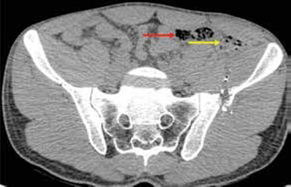

En este mismo grupo de 14 pacientes operados, 12 tuvieron lesiones que requerían manejo quirúrgico; en dos (el 4 y el 8), la laparotomía no fue terapéutica (figuras 4 y 5); en tres, el abdomen no se pudo evaluar, aunque había estabilidad hemodinámica, por lo cual se les practicó TC; el número 1 tenía politrauma, llegó intubado y sedado a la institución, al igual que el número 12; el número 2 tenía trauma raquimedular asociado.

En 48 de los 62 pacientes se optó por un manejo no operatorio por los hallazgos de la TC. En dos de ellos, sometidos a cirugía temprana por criterio del cirujano, la laparotomía fue terapéutica: en uno, hubo trauma grado II en espejo en el intestino delgado que debió ser corregido y, en el otro, trauma grado II de recto intraperitoneal que debió ser corregido y se acompañó de colostomía. En este último paciente el protocolo de la TC fue incompleto por ausencia de medio de contraste rectal. Estos dos pacientes no presentaron complicaciones posquirúrgicas.

En este mismo grupo de 48 pacientes sin indicación quirúrgica inicial, otros tres debieron intervenirse quirúrgicamente después de un tiempo de observación clínica por presentar dolor no controlado. Dos de ellos presentaban heridas toracoabdominales derechas; en uno, los hallazgos quirúrgicos fueron trauma hepático de grado II, hemoperitoneo de 300 ml y lesión del hemidiafragma derecho y, en el otro, lesión del hemidiafragma derecho y trauma hepático de grado II, por lo cual sus intervenciones se consideran no terapéuticas (verdaderos negativos, figuras 6 y 7). El tercer paciente no presentaba lesiones viscerales. Ninguno de los tres sufrió complicaciones posquirúrgicas. Los restantes 43 pacientes fueron dados de alta sin complicaciones después del tratamiento no operatorio.